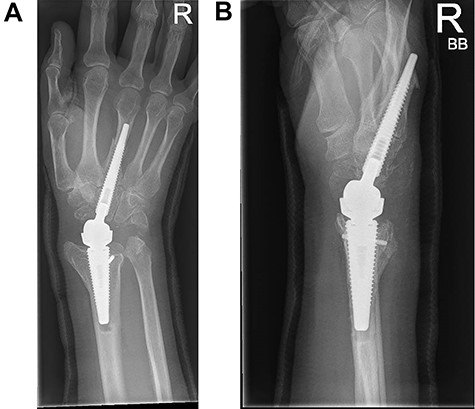

A 52-year-old female patient presented following failed fixation of a left distal radius fracture. She had undergone surgical fixation of a distal radius fracture 8 years previously and now complained of persistent and continuous pain, restricted range of movement and functional limitation. Her imaging confirmed a healed distal radius fracture in neutral alignment but with evidence of degenerative change in the radiocarpal joint and migration of the metalwork so that the distal screws penetrated the wrist joint (Fig. 1A and B).

(A and B) PA and lateral radiographs showing failed distal radius fixation with radiocarpal degenerative change.